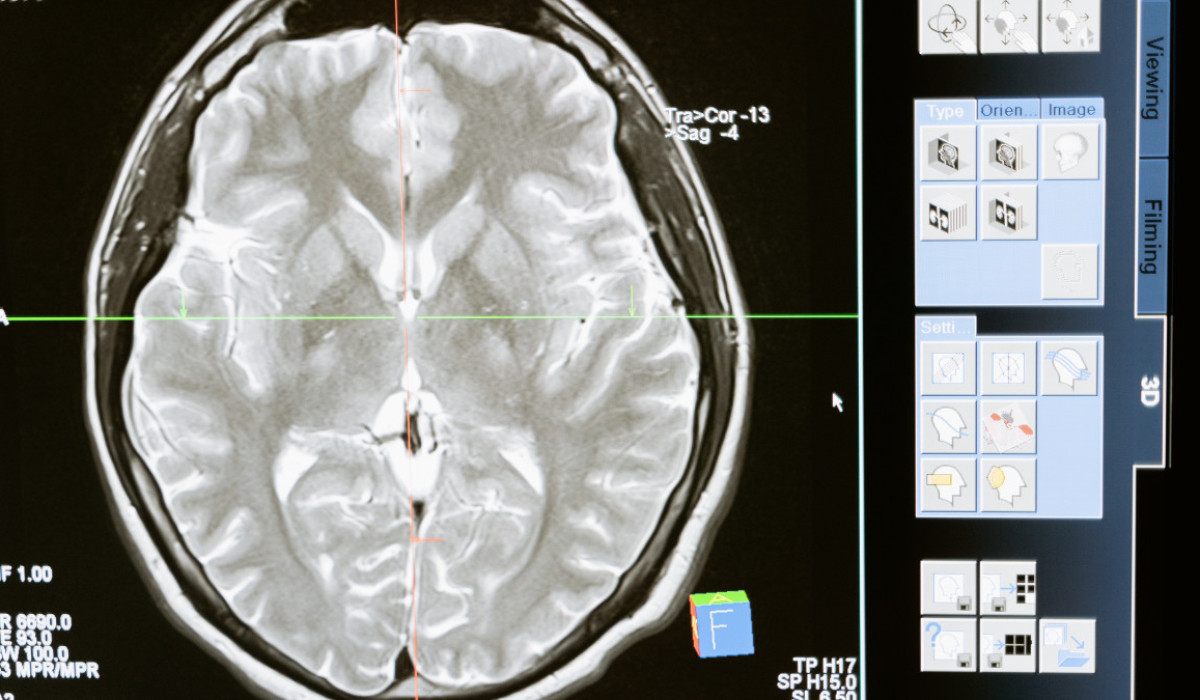

© Pexels.com

Фото: © Pexels.com